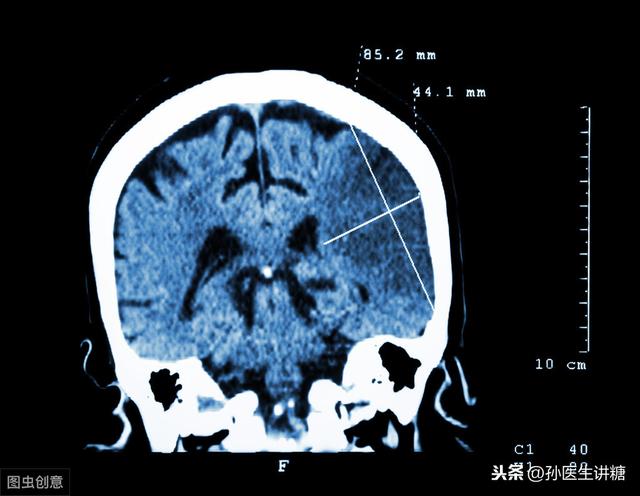

Le diabète de type 2 est étroitement lié au surpoids et à l'obésité. La pathogenèse des patients obèses est principalement la résistance à l'insuline, qui se traduit par une insensibilité des cellules graisseuses à l'insuline ; d'autre part, elle s'accompagne souvent d'une dyslipidémie, d'une augmentation des acides gras radicaux et d'une facilité à former une résistance à l'insuline. L'élévation de la glycémie affecte les vaisseaux sanguins dans tout le corps, provoquant une sclérose vasculaire, un ralentissement du flux sanguin, une augmentation de l'agrégation plaquettaire, la formation d'un thrombus, le blocage des vaisseaux sanguins cérébraux, et plusieurs facteurs se synergisent pour finalement provoquer une thrombose cérébrale. Dans les cas bénins, elle affecte la qualité de vie des patients, et dans les cas graves, elle met leur vie en danger.

Plus grave encore, une grande quantité de graisse pénètre également dans les vaisseaux sanguins, se dépose dans la paroi des vaisseaux sanguins et provoque la dénaturation de la graisse, ce qui détruit la structure organisationnelle normale des vaisseaux sanguins. Lorsque la dénaturation de la graisse forme des amas de plaques, les vaisseaux sanguins deviennent plus étroits, plus durs et plus fragiles, la rupture de l'obstruction peut se produire à tout moment, ce qui est la cause fondamentale de l'apparition de la maladie vasculaire cardio-cérébrale.